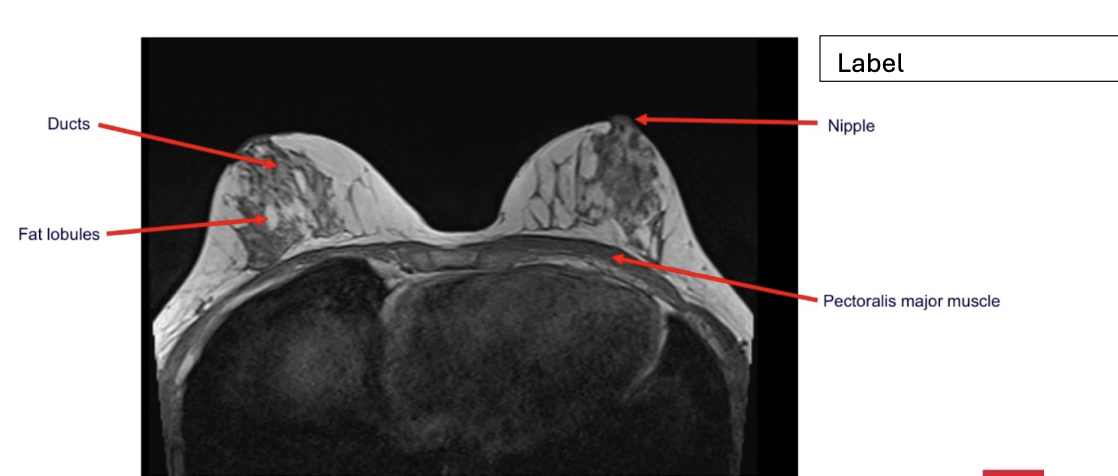

label each

2- lateral and medial condyles of femur

4- vastus lateralis muscle

5-posterior cruciate ligament

6- anterior cruciate ligament

7- medial meniscus of knee

8- lateral meniscus of knee

9-tibia

10-fibula